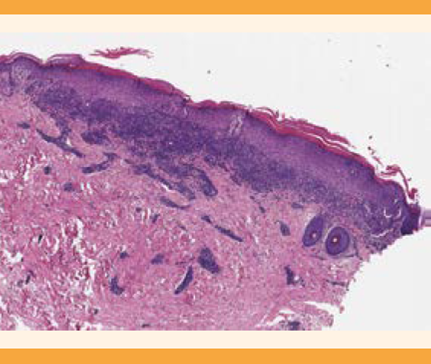

El seguimiento en la consulta de Ginecología fue a las 6 semanas, para valorar la evolución de las lesiones vulvares; se evidenció la desaparición completa de las lesiones de la mucosa vulvar, sin cambios cicatriciales, hallazgos sugerentes del diagnóstico de liquen plano vulvar, subtipo pápulo-escamoso. El reporte anatomopatológico de la biopsia fue de: hiperqueratosis e hiperplasia epidérmica, con crestas en dientes de sierra, e infiltrado linfocitario en banda, liquenoide, con queratinocitos apoptósicos asociados. El diagnóstico definitivo fue: liquen plano. Figuras 4 y 5

Figura 4 Hiperqueratosis e hiperplasia epidérmica con crestas en dientes de sierra e infiltrado linfocitario en banda (hematoxilina-eosina 2xT.).